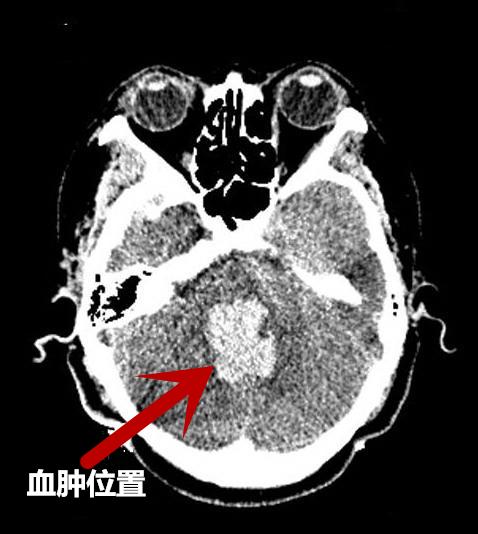

“入院时,患者意识呈深昏迷状态,血压210/116mmHg,自主呼吸急促,面色紫绀,立即行气管插管,呼吸机辅助呼吸,头颅CT提示:脑干出血破入脑室,出血量约13ml,因患者病情危急,转入神经外科ICU给予积极治疗维持生命体征。”接诊的急诊科医生回忆说。

术后复查CT,与术前CT对比血肿明显减少